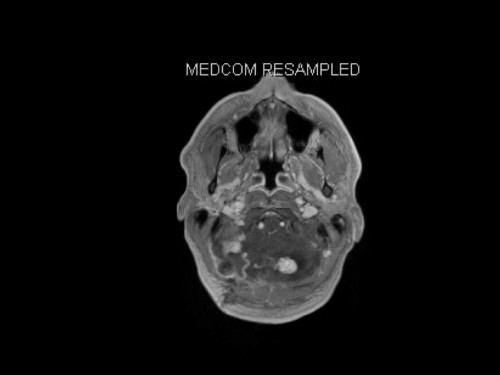

3. Schwindel und Kopfschmerzen, 3 Jahre nach Phäochromozytom-Resektion

Schwindel und Kopfschmerzen, 3 Jahre nach Phäochromozytom-Resektion

19-jähriger Mann. Er klagt seit mehreren Wochen über Schwindel und Kopfschmerzen. Im Alter von 16 Jahren sind er und sein Zwillingsbruder an einem Phäochromozytom operiert worden.